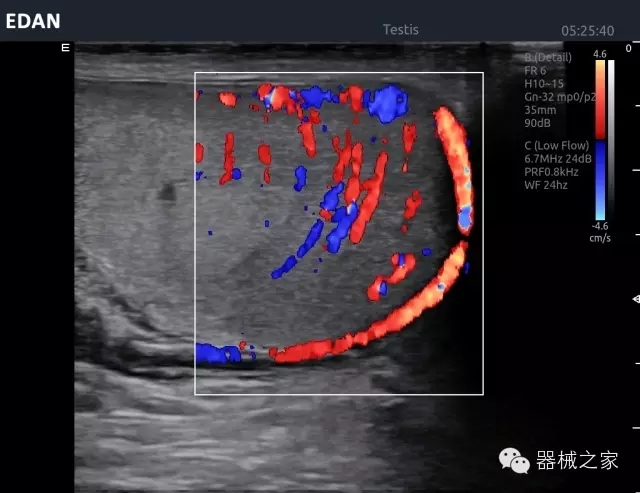

經(jīng)典產(chǎn)品:Acclarix AX8

臨床圖片賞析

睪丸低速血流